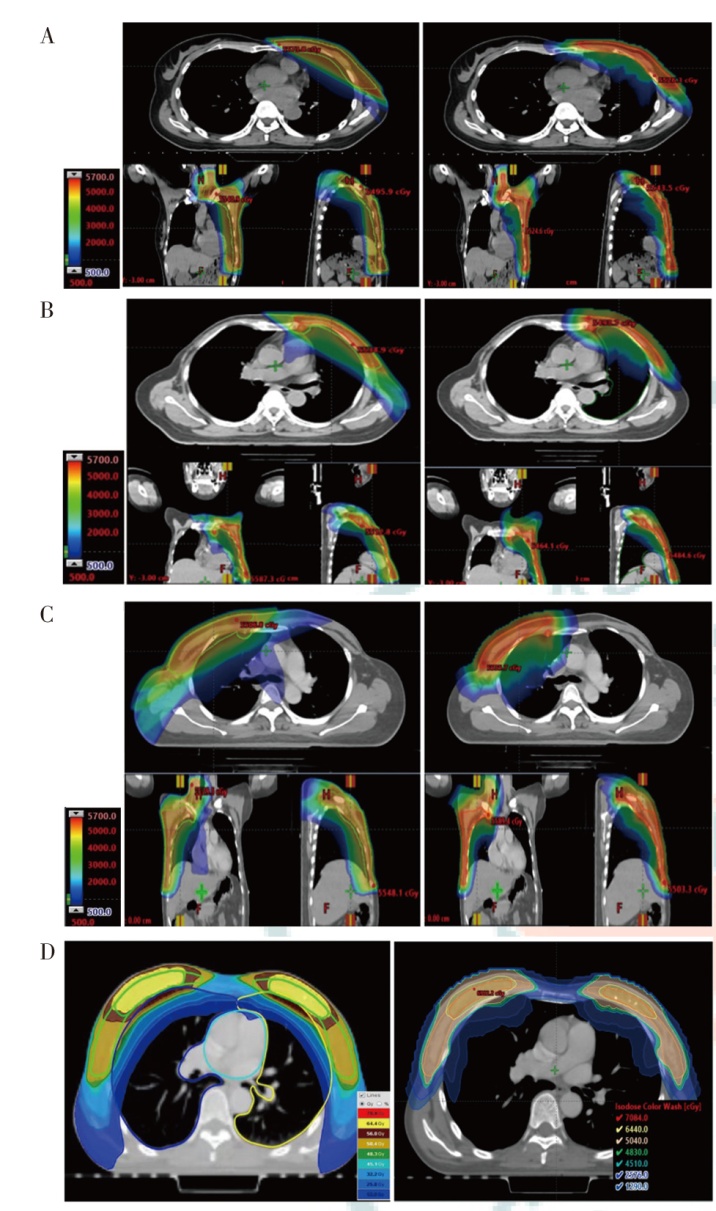

目的探索质子放疗和光子放疗应用于乳腺癌治疗的剂量学特点。方法选取2024年1月至2024年5月在山东省肿瘤防治研究院(山东省肿瘤医院)需行放疗的4例女性乳腺癌患者为研究对象,靶区范围分别为左侧胸壁加左侧锁骨上下淋巴引流区、左侧胸壁加左侧内乳、锁骨上下淋巴引流区、右侧胸壁加右侧内乳、锁骨上下淋巴引流区和双乳腺并瘤床加量。根据靶区处方剂量和危及器官限量要求,分别设计质子调强放疗(IMPT)、光子固定野调强放疗(IMRT)(双侧乳腺为螺旋断层放疗)计划。评估各计划靶区的适形指数(CI)、均匀性指数(HI)、梯度指数(GI)及危及器官受量,对比IMPT和光子放疗的剂量学特点。结果4例乳腺癌患者的IMPT和光子放疗计划均能满足临床要求,其中IMPT计划HI值(0.10~0.14)与光子放疗计划(0.10~0.12)相当,光子放疗计划的平均CI较IMPT计划高0.10,平均GI较IMPT计划低0.55。IMPT计划的患侧肺和心脏的Dmean更低,特别在低剂量区域(V0-3)显著少于光子放疗计划;患侧肺的Dmean分别降低了12.2%、6.1%、16.1%和34.8%,心脏的Dmean分别降低了47.2%、57.0%、72.4%和83.0%。IMPT计划的患侧肺V20并不比光子放疗计划更低(单侧乳腺:IMPT为30.0%~34.0%,IMRT为29.0%~35.9%)。结论IMPT在保证乳腺癌靶区覆盖的情况下显著降低了患侧肺和心脏的Dmean,使更多区域不受照射、保护周边更多的正常组织。但是在患侧肺的V20方面,IMPT并未表现出比光子放疗计划更有优势。